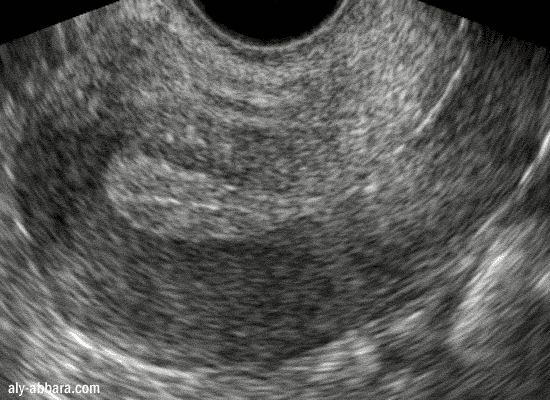

Endomètre d'épaisseur normale au 12éme jour du cycle menstruel

Endomètre de 9 mm d'épaisseur